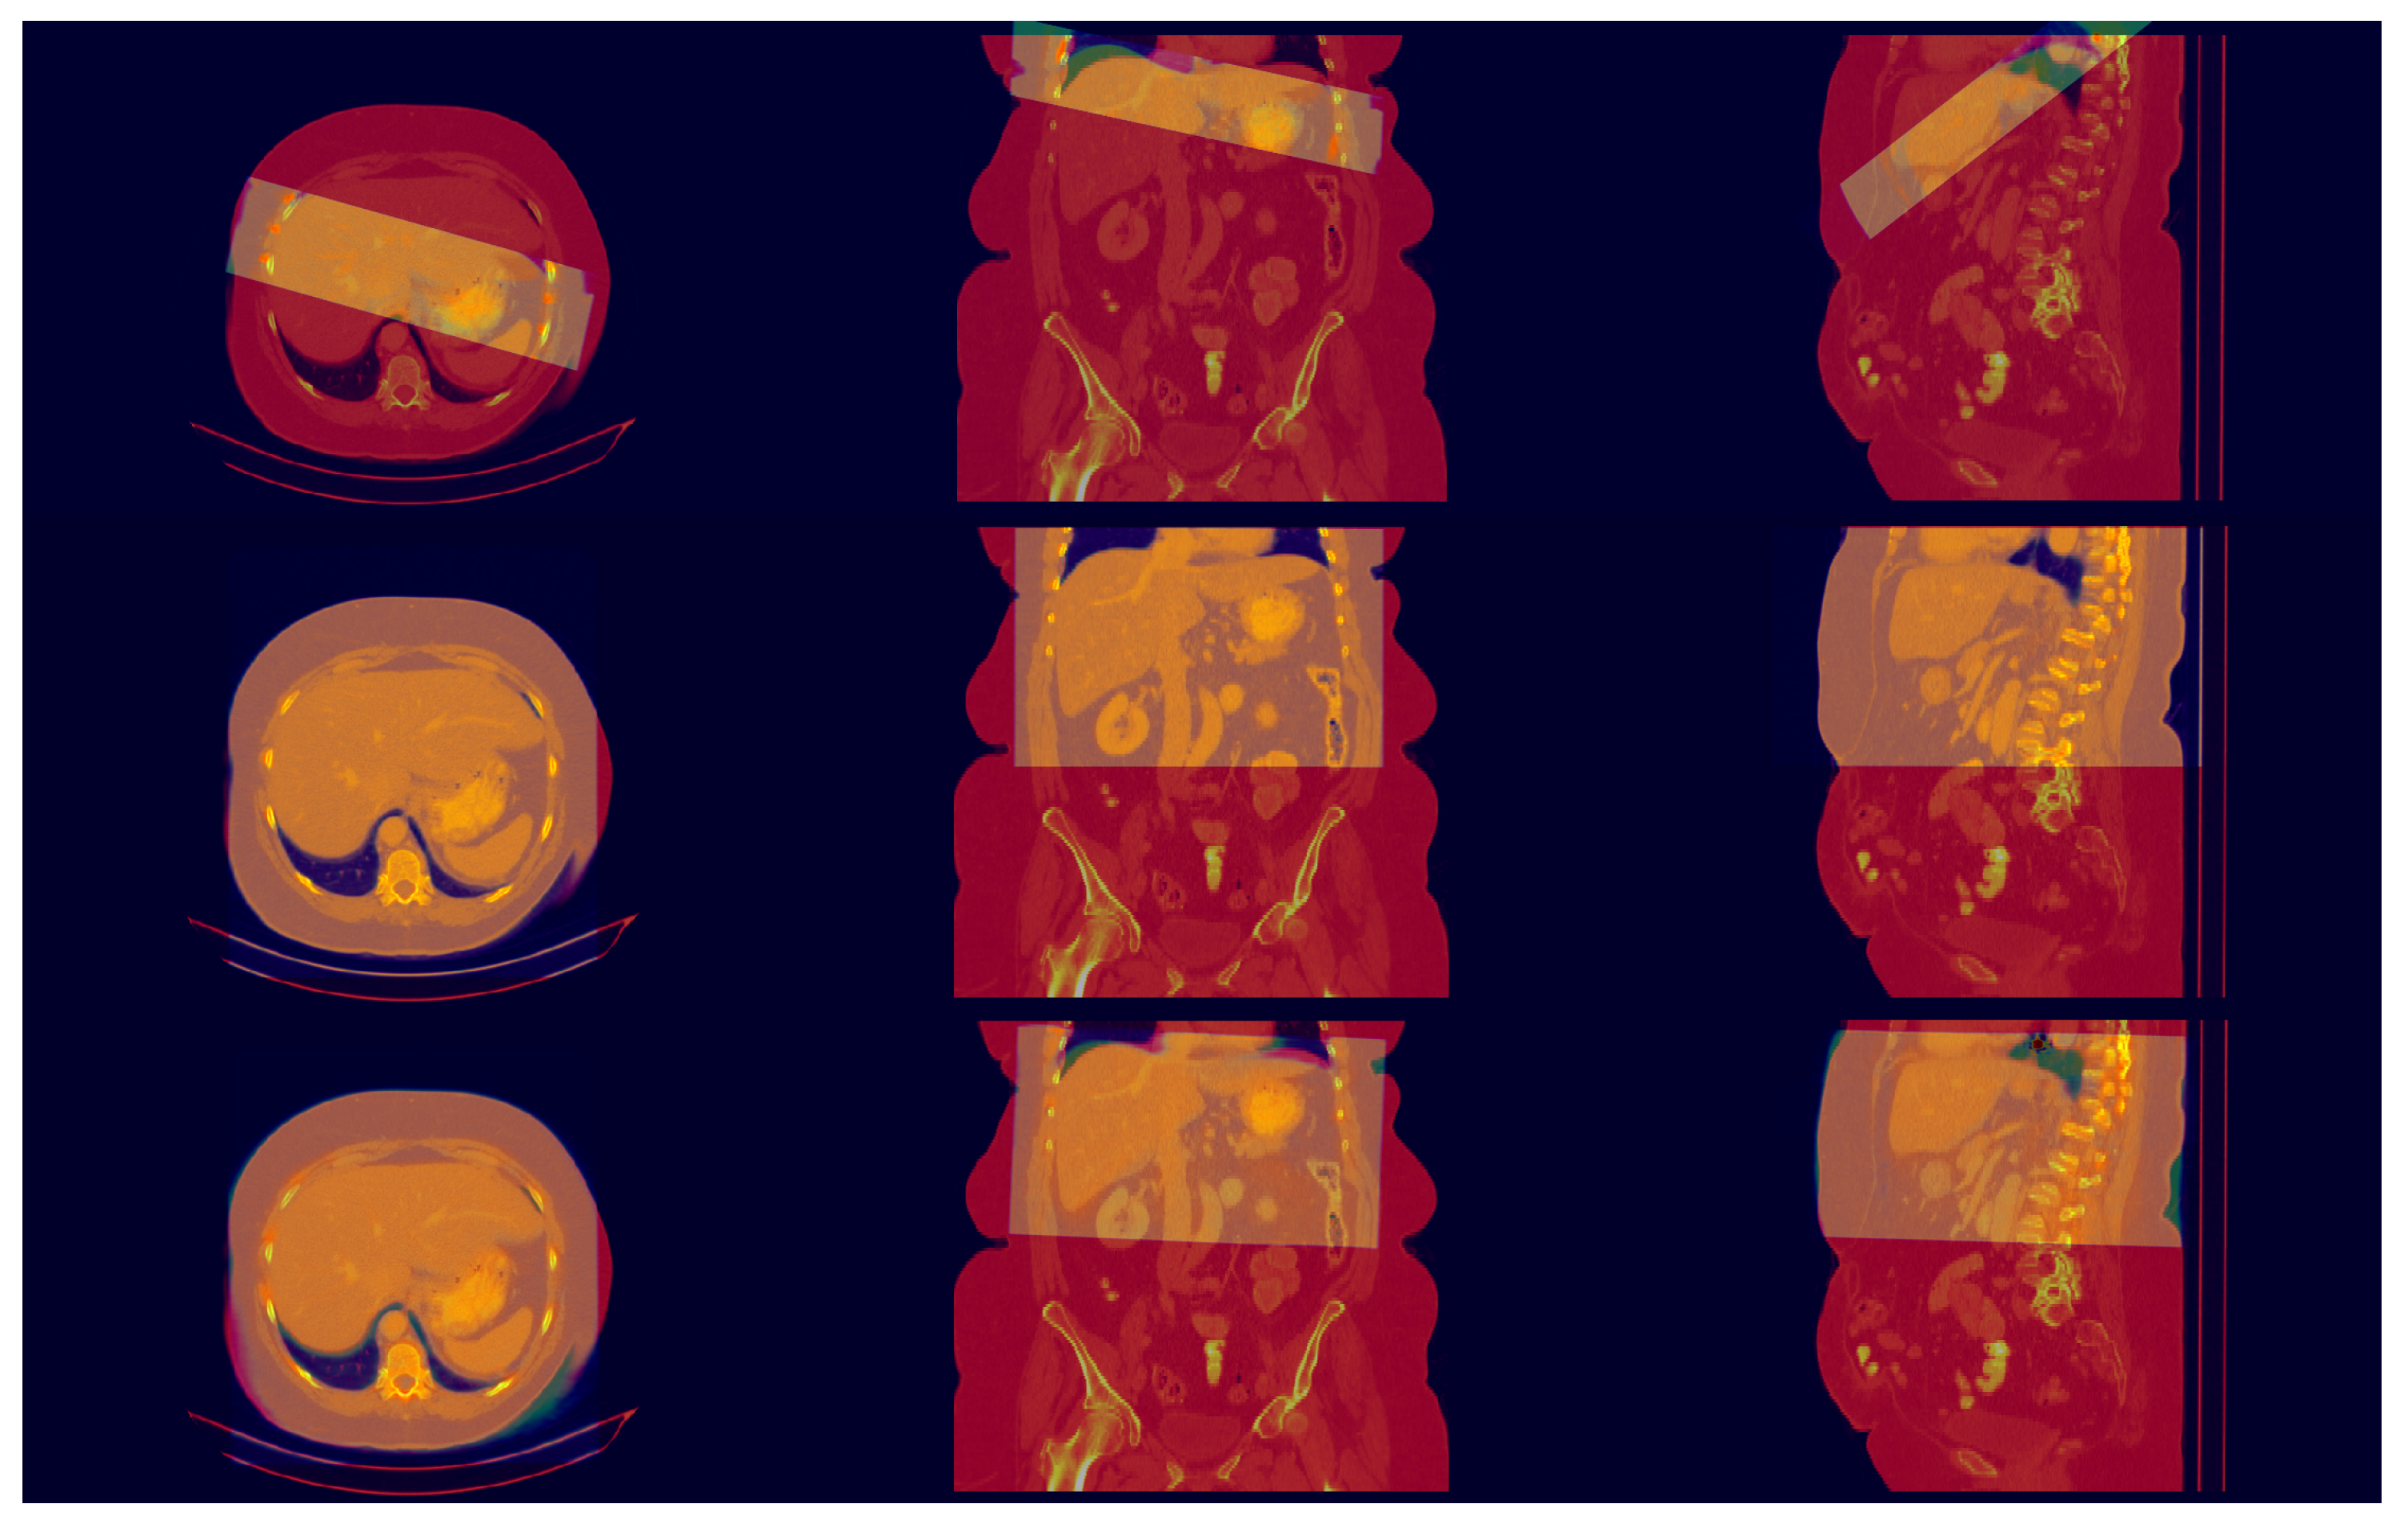

2. Materials and Methods

2.2. Proposed Method

3. Results

3.2. Registration Test